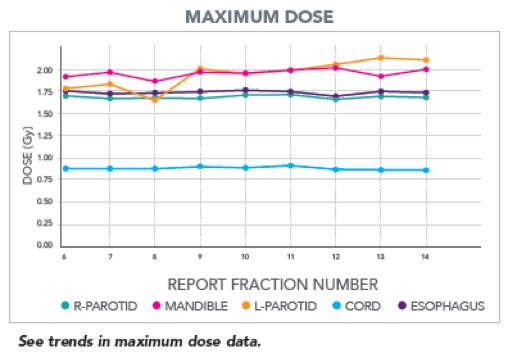

II. Αυτόματη παρακολούθηση της χορηγούμενης ακτινοθεραπευτικής αγωγής

Το σύστημα περιλαμβάνει εργαλεία που επιτρέπουν στον ακτινοθεραπευτή ιατρό να παρακολουθεί την εκτέλεση της ακτινοθεραπείας και να ενημερώνεται αυτόματα για τις περιπτώσεις εκείνες που απαιτείται αναπροσαρμογή του πλάνου θεραπείας.

Το σύστημα περιλαμβάνει εργαλεία που επιτρέπουν στον ακτινοθεραπευτή ιατρό να παρακολουθεί την εκτέλεση της ακτινοθεραπείας και να ενημερώνεται αυτόματα για τις περιπτώσεις εκείνες που απαιτείται αναπροσαρμογή του πλάνου θεραπείας.

- Ενημέρωση της ηλεκτρονικής καρτέλας του ασθενούς για την δοσιμετρική ακρίβεια της χορηγούμενης ακτινοθεραπείας

- Ενημέρωση του ακτινοθεραπευτή ιατρού στην περίπτωση που ο όγκος στόχος ή τα κρίσιμα όργανα λαμβάνουν δόση εκτός των κριτηρίων ανοχής που έχει θεσπίσει.